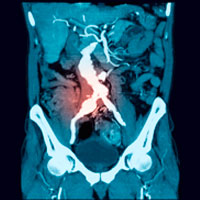

Översikt Ett aktivt och multidisciplinärt omhändertagande räddar tarm och lidande vid utbredd bukvenstrombotisering

Klinik och vetenskap Evidensen för screening för bukaortaaneurysm av män > 65 år är god. Antale…

Medicinsk kommentar Både öppen och endovaskulär teknik försvarar sin plats